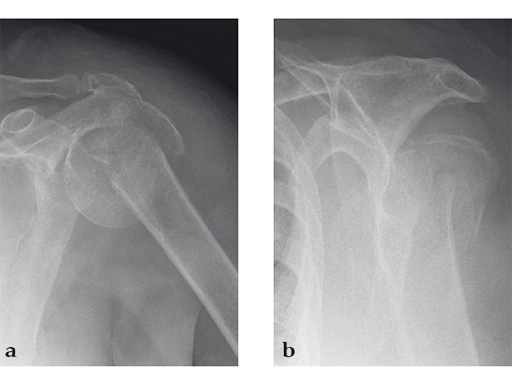

Case 1: A three-part valgus impacted fracture of the proximal humerus in a 47-year-old woman.

Case 2: Three-part valgus displaced fracture of the proximal humerus in a 63-year-old man.

Case 4: AO 12C1 fracture following fall

A 54-year-old woman, and otherwise healthy patient, fell during her holidays and sustained an AO 12C1 fracture. There was no major soft tissue trauma. Other lesions: avulsion at the 5th metatarsal base, and concussion. Surgery took place on day 9 after the accident. The patient left the hospital the day after surgery.